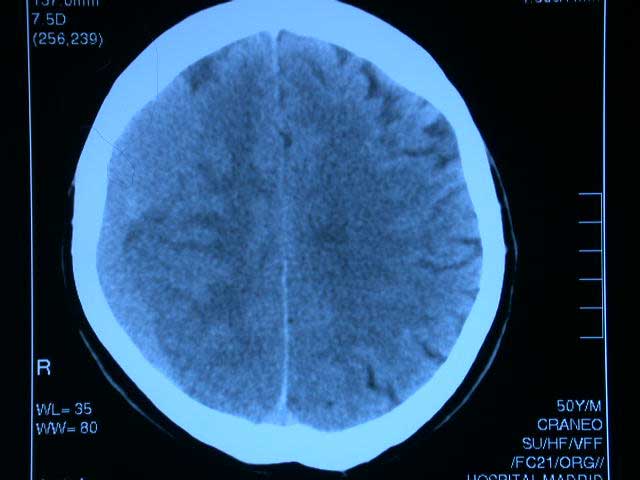

Warfarina superior a rivaroxabán en pacientes con sindrome antifosfolípido de alto riesgo

30 octubre 2018

El ensayo clínico se finalizó en forma prematura por el aumento de la tasa de eventos tromboembólicos en los pacientes con rivaroxabán en comparación con warfarina. Blood, septiembre de 2018